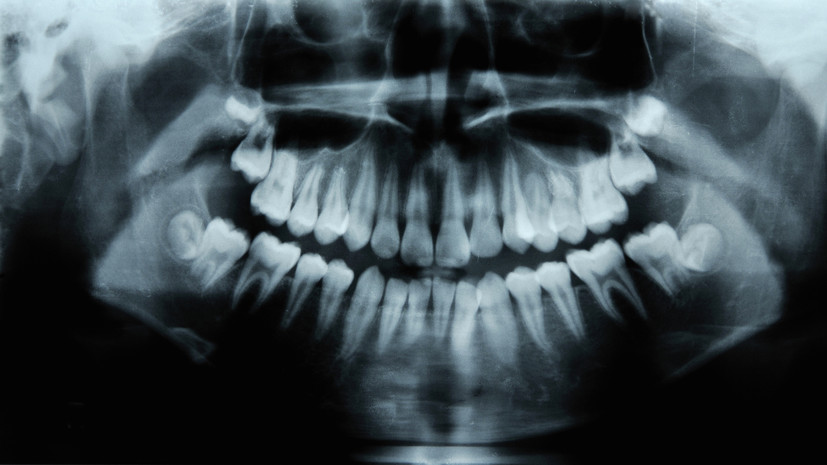

- Gettyimages.ru

Стоматолог объяснил, что из-за позднего появления зубам мудрости часто не хватает пространства для роста, потому что размер челюсти современного человека постепенно уменьшается.

По его мнению, в 99% случаев форма лица после удаления зуба мудрости не меняется, если они не прорезались или встали неправильно в зубном ряду.